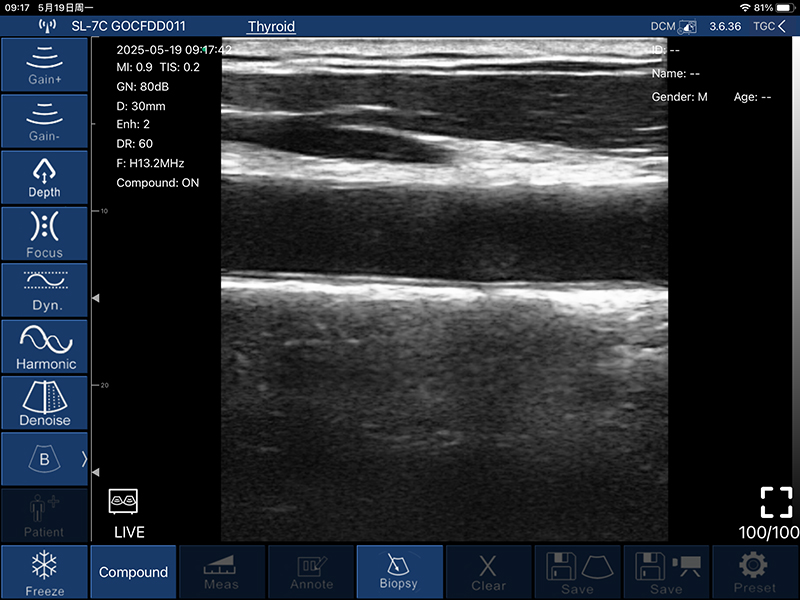

• B模式

增益:30db-105db

降噪:0-1-2-3-4

动态范围: 40-50-60-70-80-90-100-110

• 穿刺辅助功能:平面内穿刺引导线功能,平面外穿刺引导与血管自动测量功能